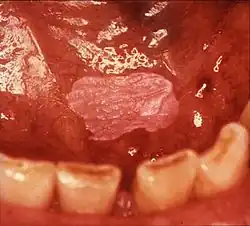

![]() | |

Leukoplakia on the inside of the cheek | |